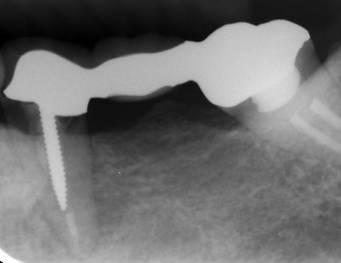

ストローマンインプラントとスプラインインプラントが隣り合わせに埋入されています.このころストローマンからスプラインに変えています。変えた理由は前歯部の審美性に優れていること、アバットメントの自由度があること、抜歯後すぐに埋入できるなどでした。

ストローマンインプラントとスプラインインプラント

術前